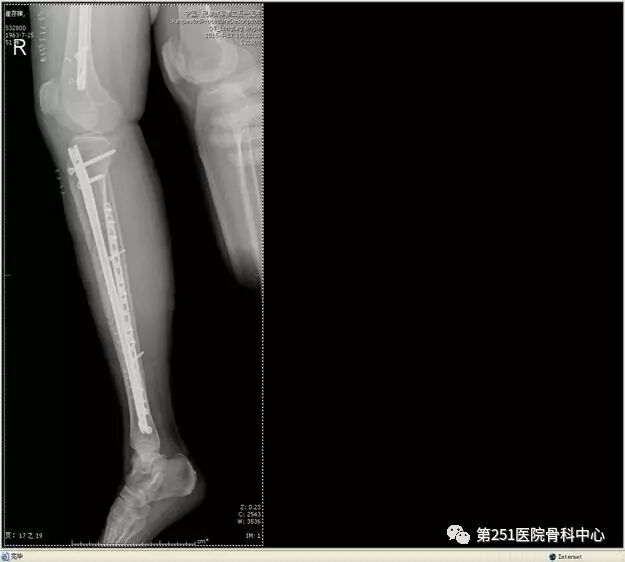

病例2:男性,44岁,车祸伤,双侧胫腓骨骨折(左侧)。

![]()